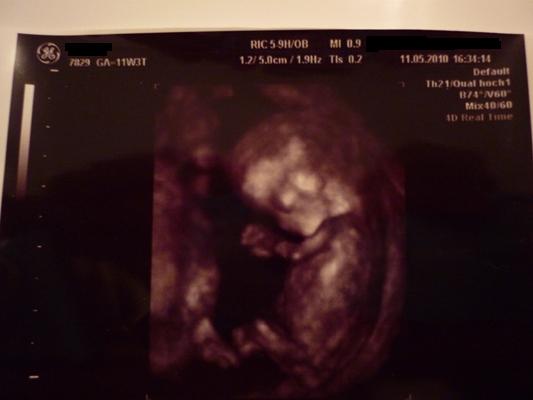

@conny: Ich stell mal gleich ein Bildchen von unserer Madame rein.Ich wollte getsren eigentlich schon aber war mir doch sehr unsicher da hier leider wieder ein paar negativs reingeflattert sind!